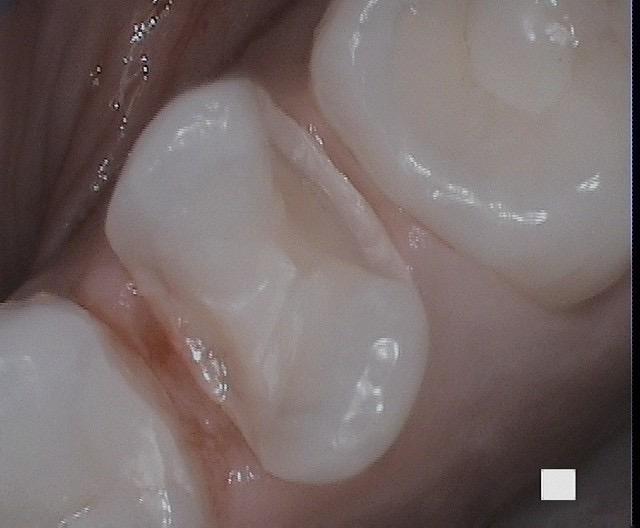

Porcelain Inlay with CEREC one visit restoration in less than 2 hours!

A bicuspid tooth with mesial open contact and distal caries was restored properly with Porcelain Inlay with CEREC one-visit restoration in less than 2 hours! An inlay is used when the cavity is too large for simple filling. The inlay is created as a single solid piece of Porcelain to fill the cavity. The inlay is precisely made in the shape and size of the cavity space. It is cemented on the tooth. Because inlays are created from highly durable materials such as gold or porcelain, they are designed to last longer than traditional fillings and be more resistant to damage and degradation.